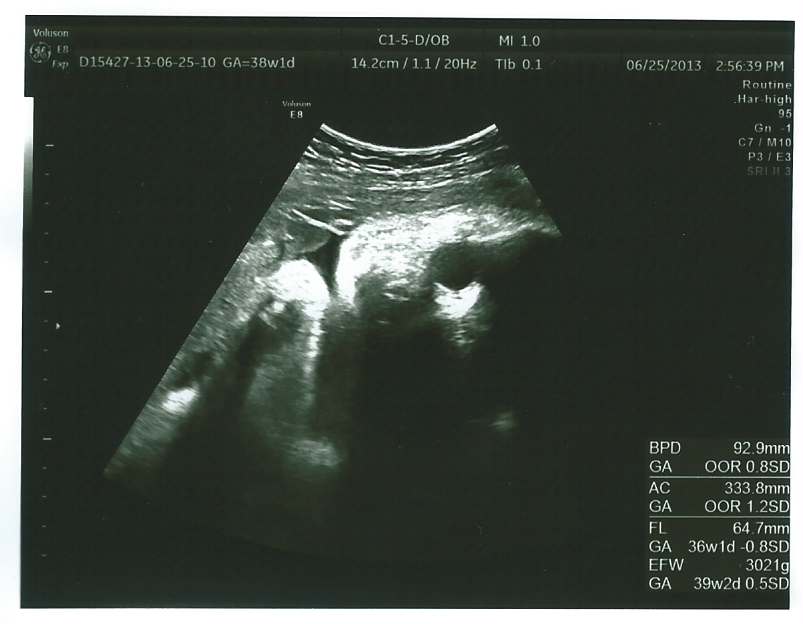

echo